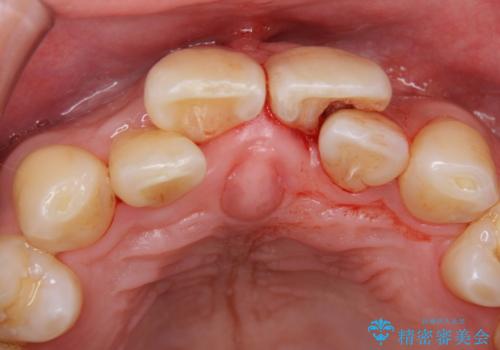

- 前歯の重なったところが虫歯になり、物理的にアプローチが難しい状態でした。

矯正治療前に虫歯を取り、歯並びが良くなってから本格的にセラミック治療を行いました。